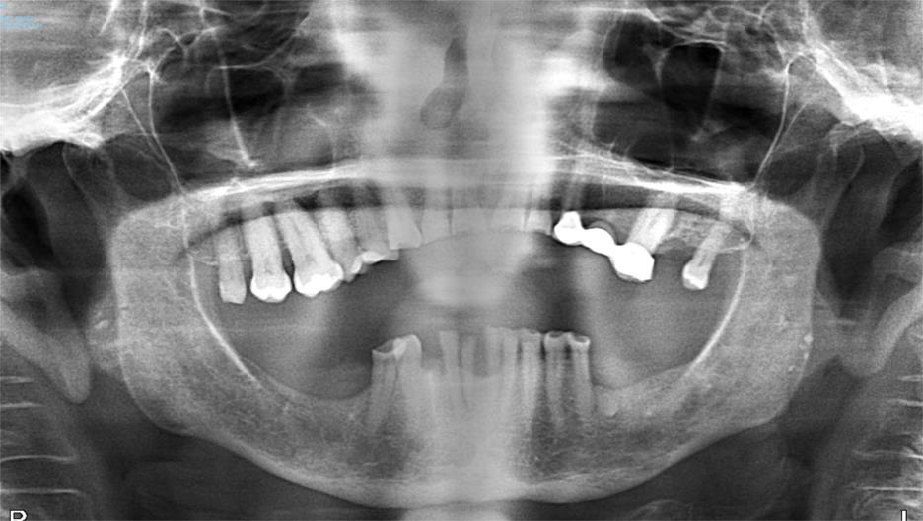

The patient is an 80-year-old female with a history of osteoporosis for which she received Alendronate (Fosamax) 70 mg one time per week for 12 years. She stopped the medication in December 2023. She was initially seen at Denver Health in January 2024 with concerns of pain and swelling on the lower right side that had persisted for over 10 months. Her dentist had removed tooth #28 and placed an osseo-integrated implant in 2020.

The patient was noted to have extensive erosive bony changes in the right mandibular body. She was diagnosed with Stage 3 MRONJ. The mandible was resected through a submandibular approach and a reconstruction bar was placed. She is now doing well without recurrence of her MRONJ and has elected not to have definitive bony reconstruction.